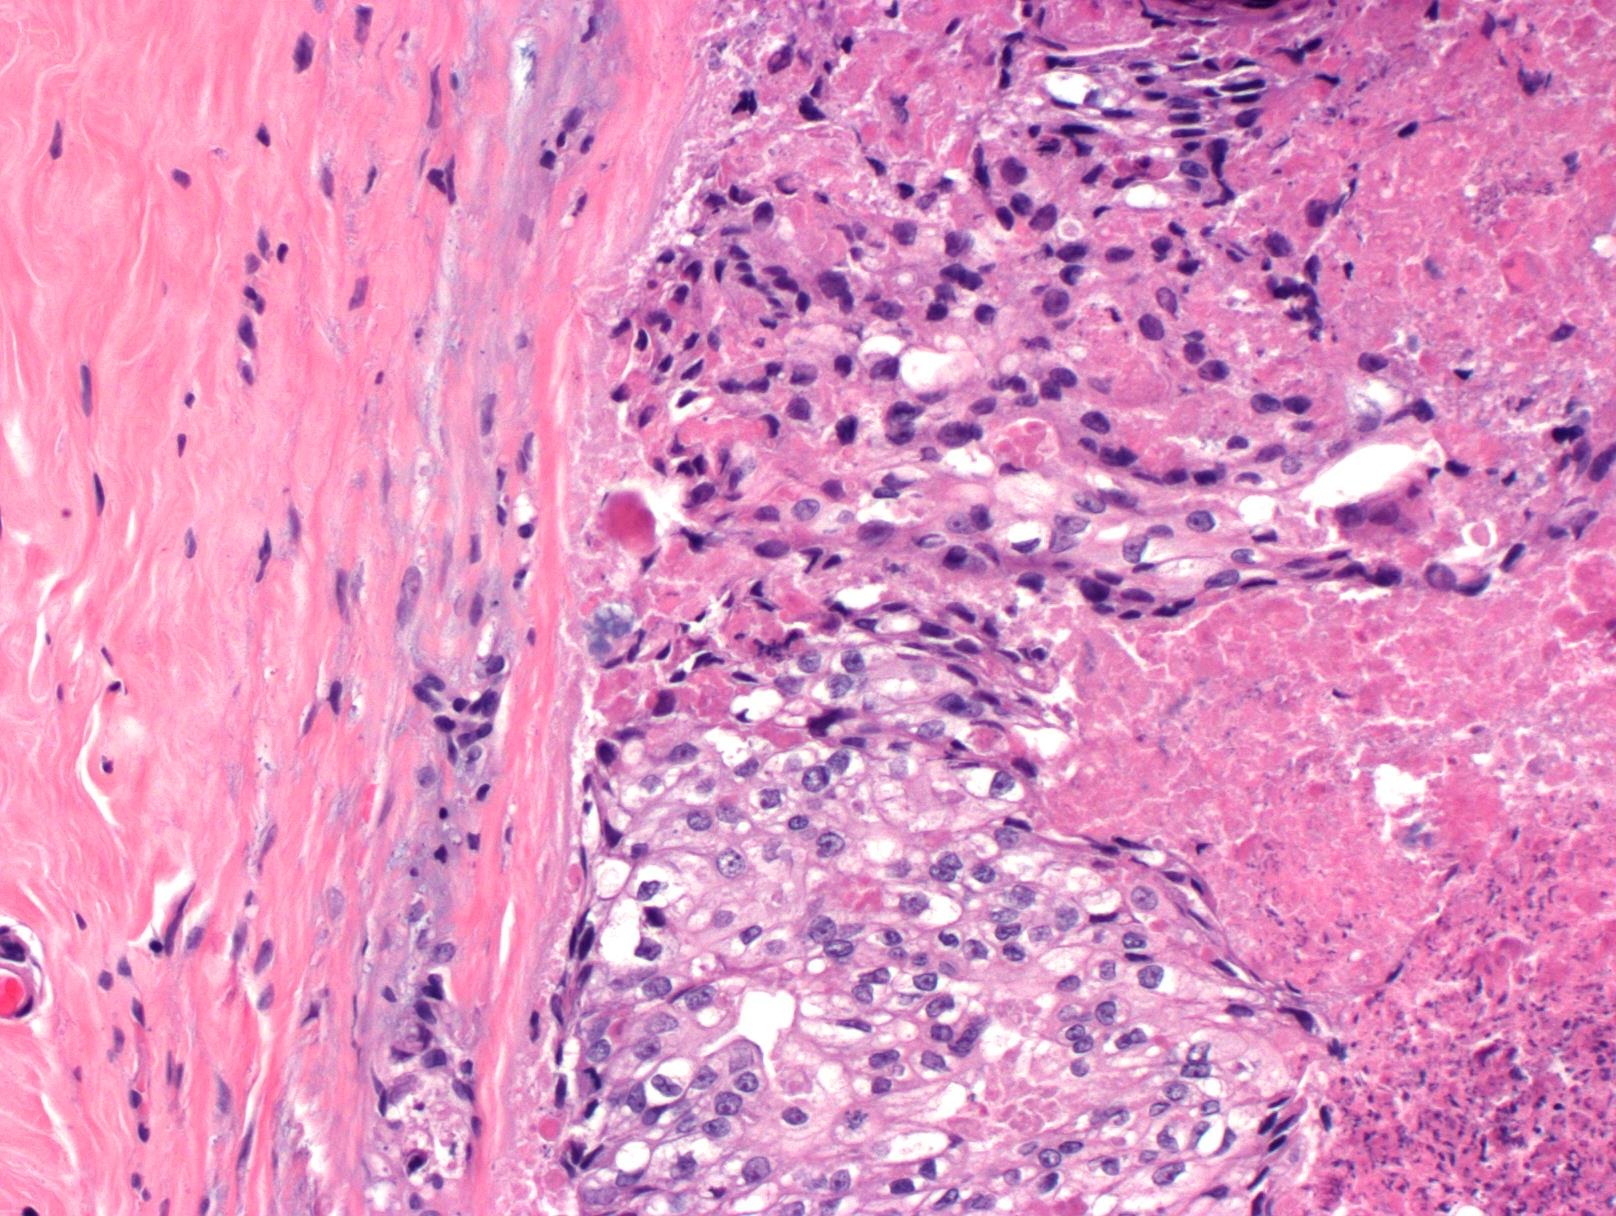

In late May 2025, after an insurance change, I scheduled a routine mammogram and was able to get one the same day. Two days later, I was notified of abnormal results. After a diagnostic mammogram and biopsy, I was diagnosed with DCIS—Stage 0 breast cancer, grade 2. An MRI later confirmed the diagnosis and showed a broader area of concern. This all happened just weeks before I competed at APO Nationals in powerlifting, which I went on to complete before beginning the next phase of appointments and planning. Because I qualified for APO Worlds, my oncologist and I agreed it was reasonable to delay a double mastectomy until after November while managing the cancer with medication. Training and competing during treatment was extremely difficult, but I did it.